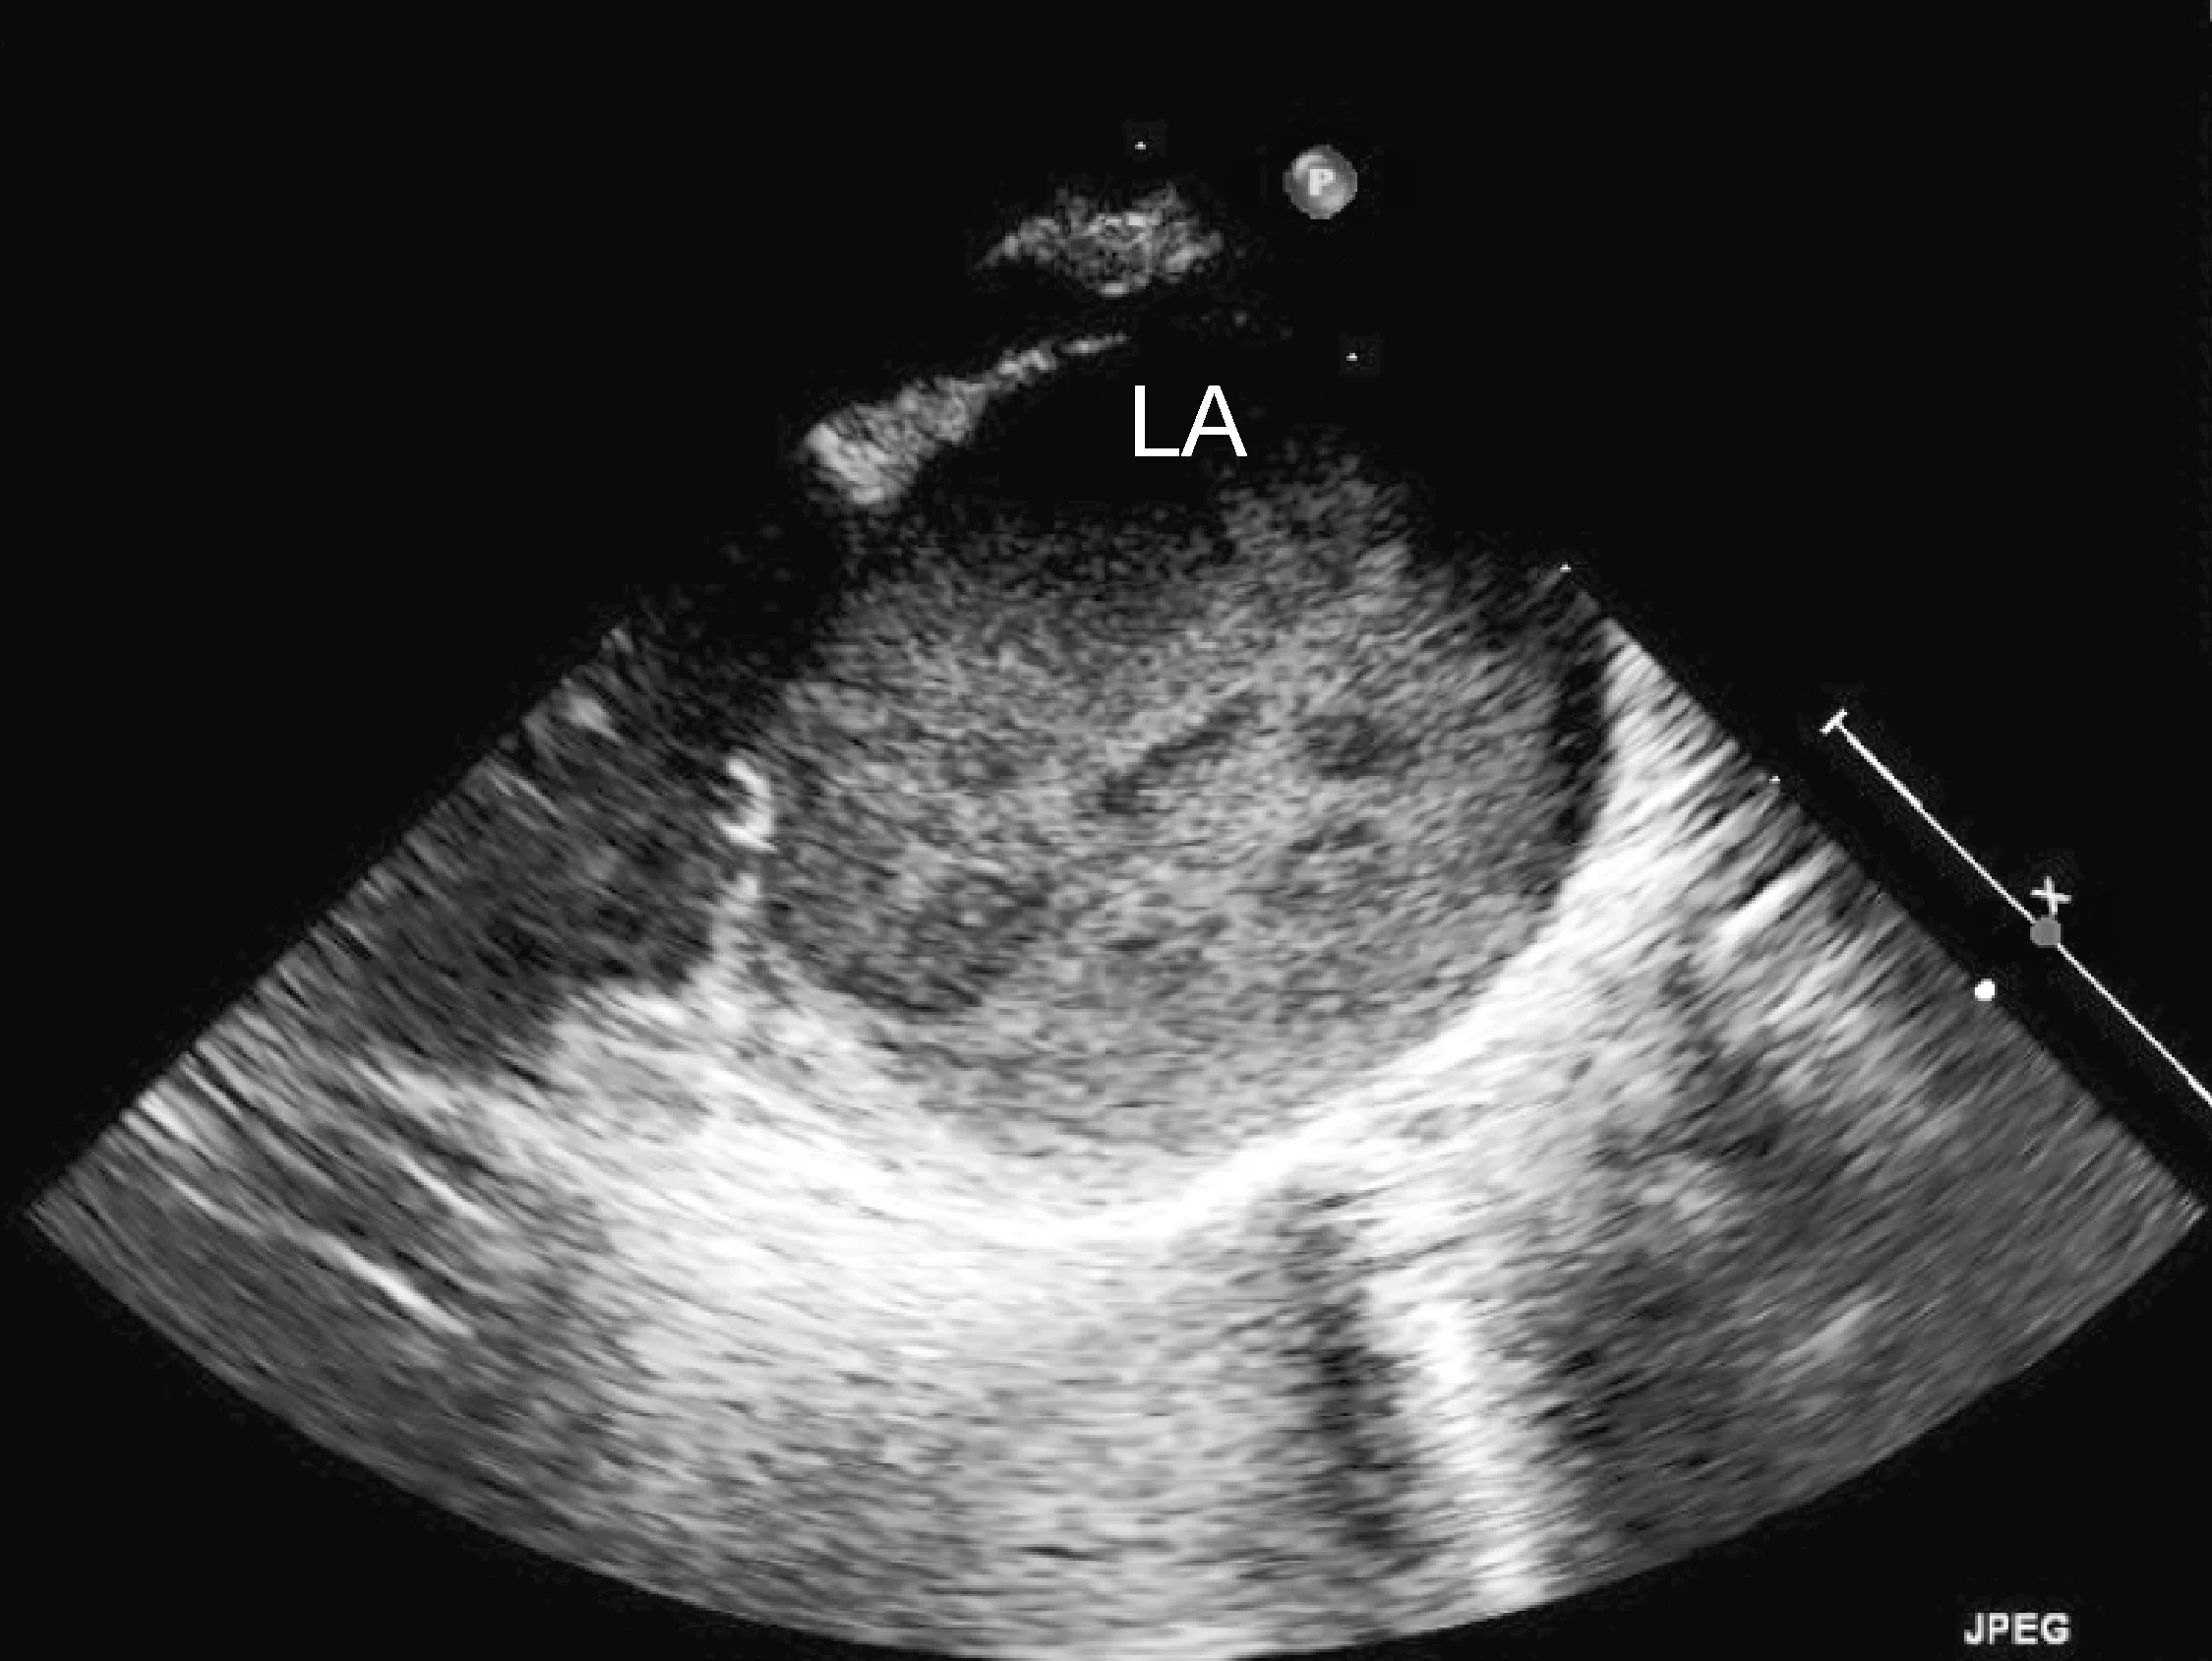

Marked left atrial enlargement was present on echocardiography after stabilization and pain management (see Treatment). A formed thrombus was apparent within the left auricle (Figure 4) and spontaneous echo contrast or smoke was present within the left atrium (Figure 5). This spontaneous echo contrast is often seen with marked chamber dilation and blood stasis; although its presence is associated with an increased risk for thrombus formation, it is not a result of a formed thrombus. Thickening of the left ventricular walls was also noted (Figure 6), which is consistent with underlying hypertrophic cardiomyopathy.

Right parasternal oblique long-axis echocardiographic view showing spontaneous contrast smoke within the left atrium (LA)